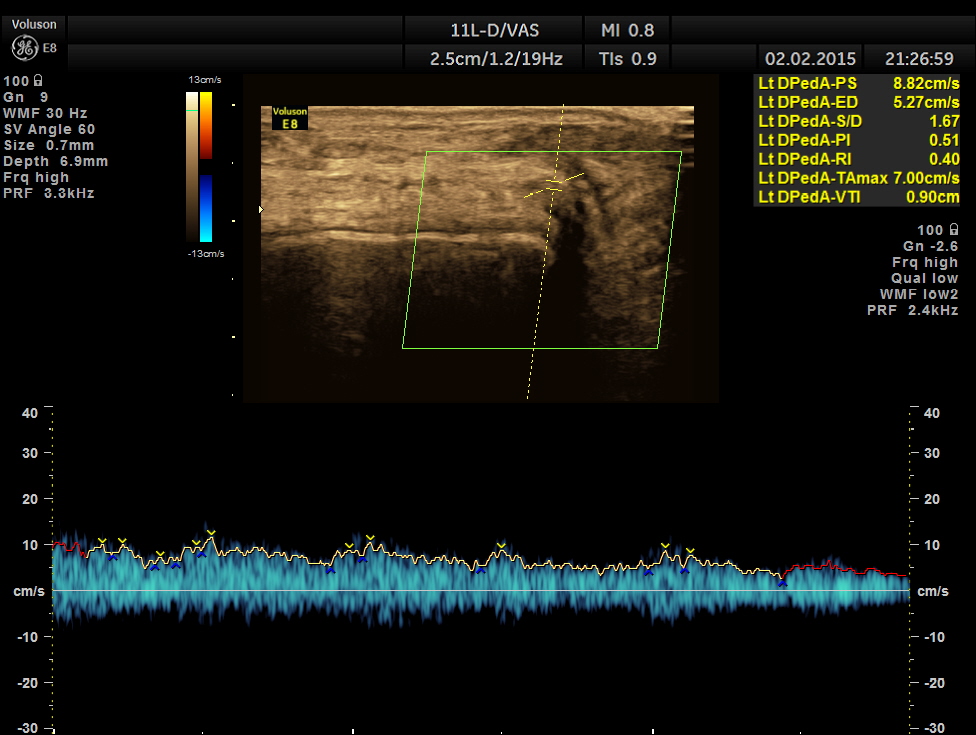

no flow was made out in the posterior tibial and dorsalis pedis arteries

you did an awesome vascular of study, you were instrumental in salvaging the patient’s limb! He didn’t develop a compartment syndrome.great case, great presentation. I’m curious as to why you don’t have 60 degree angle

Hello–thank you for posting this interesting case. I am assuming that you used no angle correction because it was an urgent exam? You certainly can see the waveform diminish in the SFA as you move inferior, however; the PW Doppler velocity measurements for the SFA are all erroneous. This must have been a difficult scan due to the patient’s pain? Thank you again for posting…